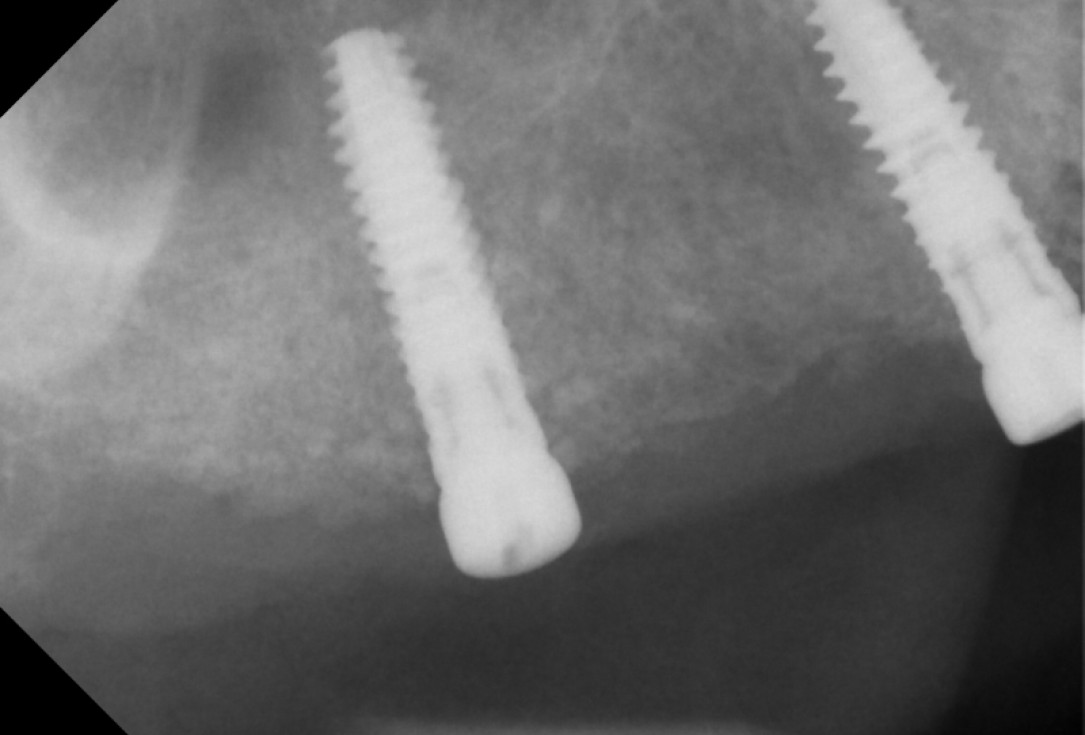

Initial x-ray showing bone loss around implants placed 5 years ago in another dental clinic